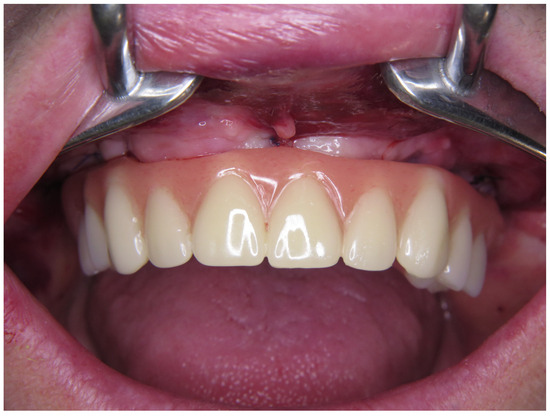

2.5. Final Prosthetic Procedure

5. Conclusions

- The advanced criteria for “success” in dental implantology were fulfilled throughout the sample after 5 years of observation for both metal–ceramic and monolithic zirconia superstructures;

- Monolithic zirconia superstructures presented superior results regarding both clinical and radiological parameters evaluated herein;